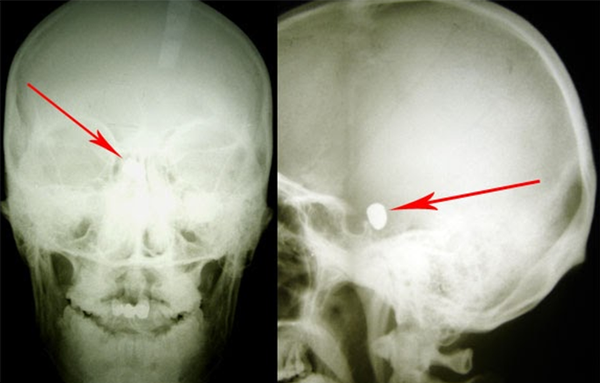

"Это не первая пуля, извлеченная в Молдове из головы пациента. Но конкретно эта операция оказалась очень сложной. Пуля проникла очень глубоко вниз и застряла в кости рядом со стволом головного мозга", — поделился подробностями проведенной им операции директор Института неврологии и нейрохирургии.

Потребовалась невероятная точность работы, ведь ствол головного мозга отвечает за жизненно важные функции, в том числе за сердцебиение и дыхание.

Дополнительная сложность — пуля находилась в голове более полутора лет, успела инкапсулироваться и "обрасти" спайками. Григорию Запухлых приходилось оперировать раненых во время вооруженного конфликта, и та работа была проще, делится он воспоминаниями. "Свежее" инородное тело хирургу извлечь гораздо легче.